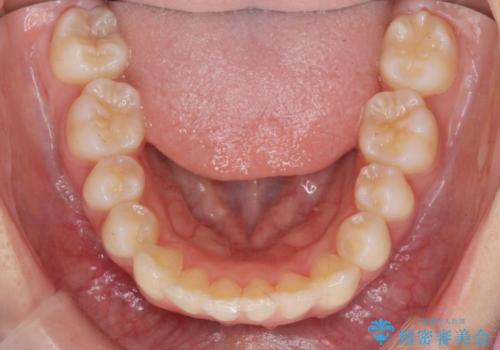

突き出た前歯の改善!マウスピースで再矯正

- 5年前にワイヤー矯正治療を終了したが、突き出たように見える前歯の仕上がりが気に入らず、再矯正治療を希望され来院されました。

マイクロインプラントを用いた遠心移動とIPRを行うことによる前歯の突出感の改善をマウスピース矯正治療で計画します。

突出していた前歯の角度が大きく改善し、審美的な仕上がりに満足いただくことができました。